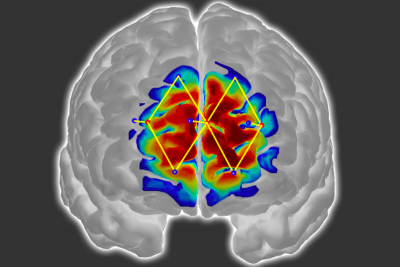

The researchers use only a few fNIRS sensors on a patient’s forehead to measure activity in the prefrontal cortex, which plays a major role in pain processing. Using the measured brain signals, the researchers developed personalised machine-learning models to detect patterns of oxygenated haemoglobin levels associated with pain responses, which predicted whether a patient is experiencing pain with around 87 % accuracy.